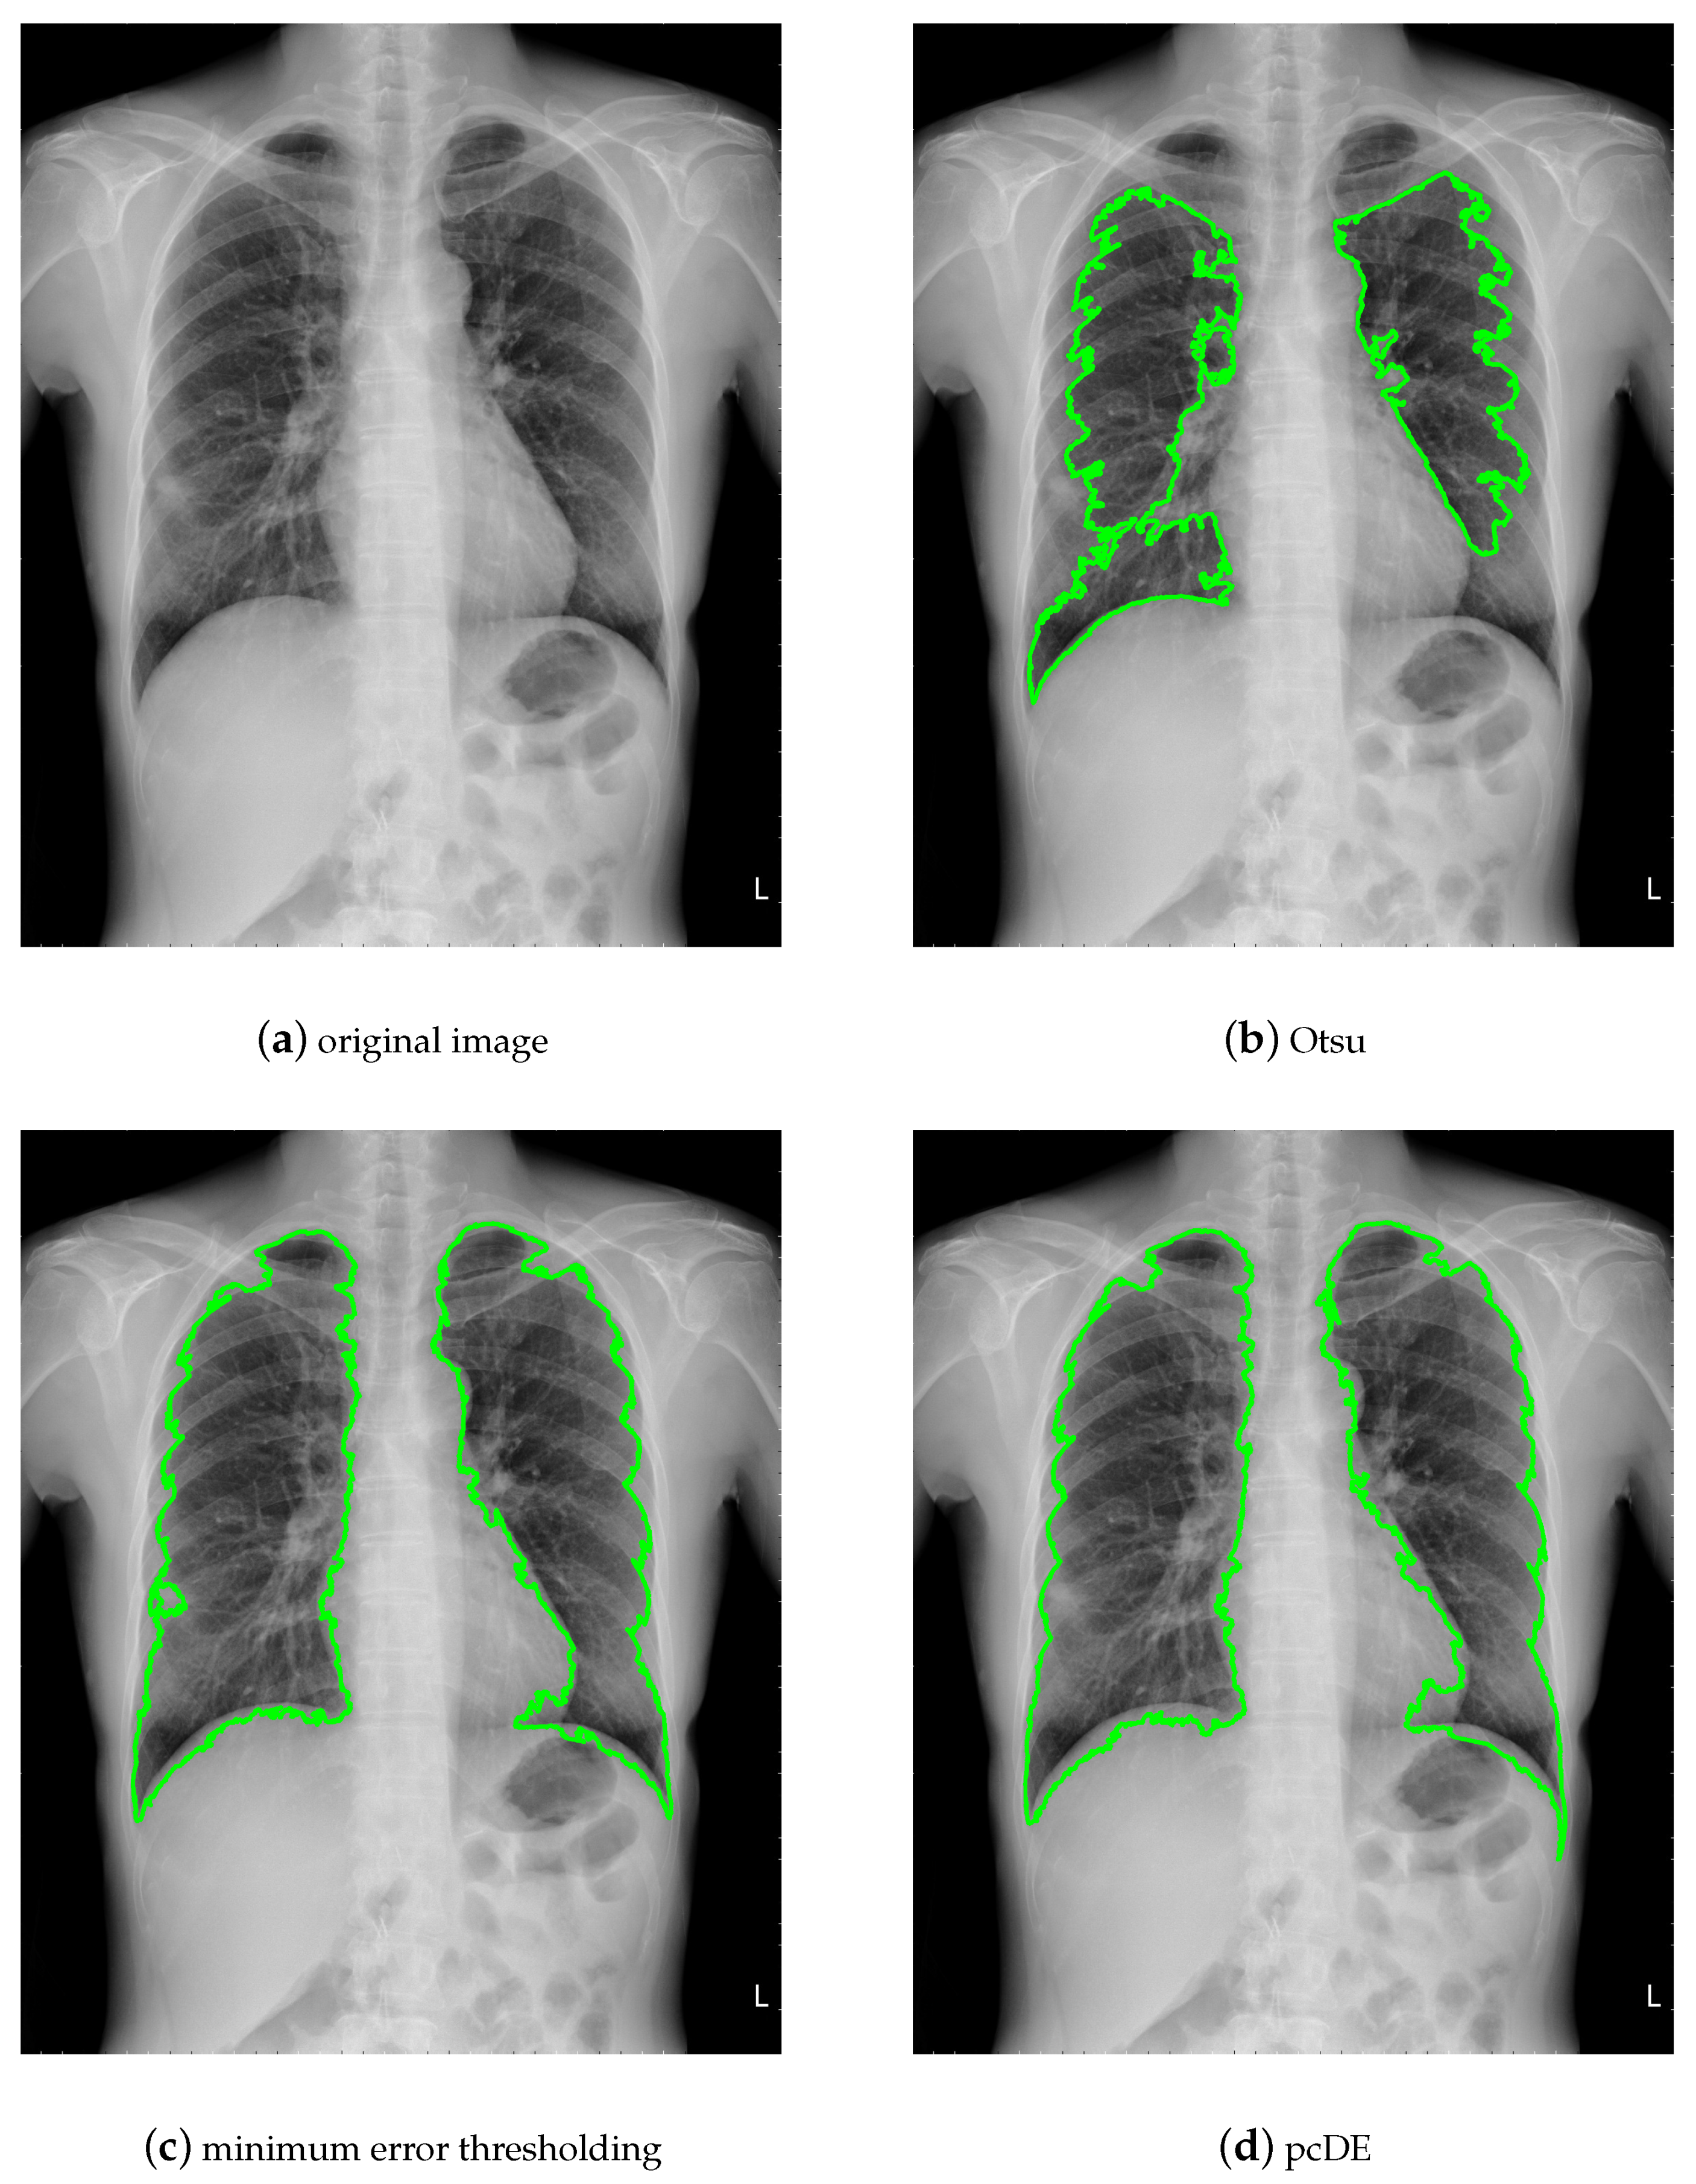

- Image preprocessing. Enhance the contrast of the image to achieve better segmentation.

- Calculate the optimal threshold for image segmentation through different methods to get the binarized image.

- Use morphological methods to process images to extract targets.

- Mark target contour.

- : Represent the result of ground truth segmentation (Figure 13).

- : Represent the result of algorithm segmentation.

| Segmentation Method | Original Image | Noisy Image |

|---|---|---|

| Otsu | 0.9210 | 0.9531 |

| minimum error thresholding | 0.9732 | 0.9093 |

| pcDE | 0.9738 | 0.9684 |